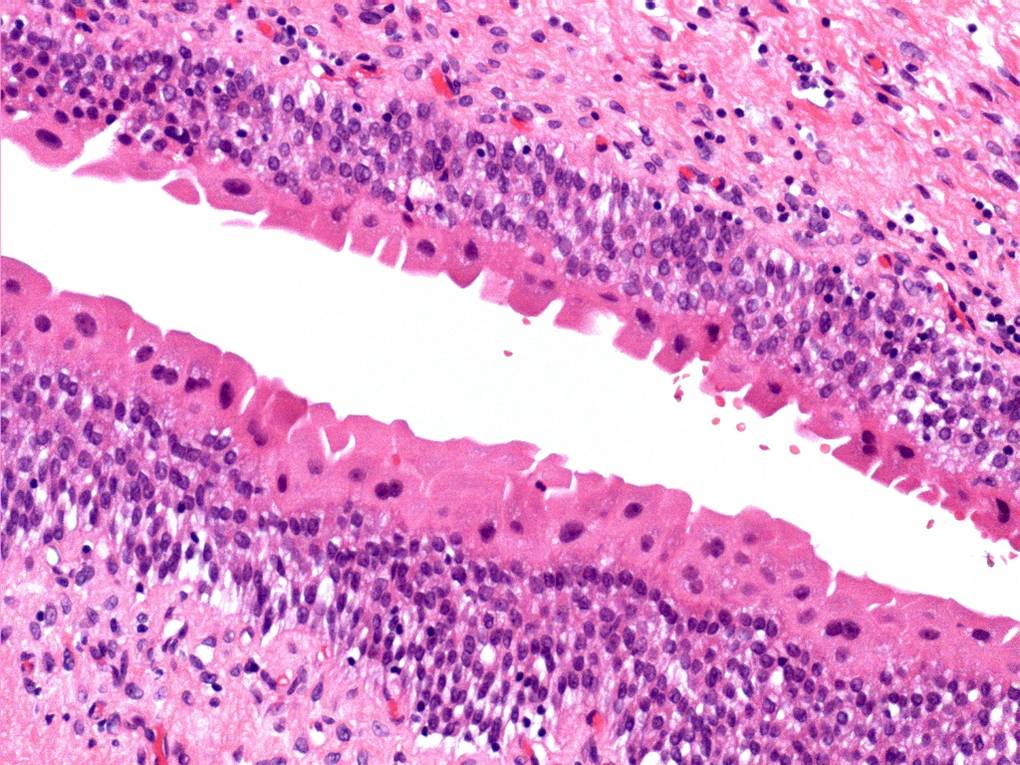

Consensus grade: Reactive atypia

The main change here is ‘degenerative’ nuclear atypia in a rather unusually prominent umbrella cell layer. The underlying urothelium shows mild reactive changes in places with some chronic inflammation in the lamina propria.